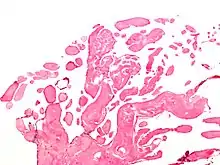

الحميد الورم المخاطي هو الورم الحميد الأكثر انتشاراً. فيشكل الورم المخاطي مامقدارة 77٪ من علميات الأورام الأولية للقلب. وهنالك أوراماً أقل شيوعاً في القلب كالورم الشحمي والورم الكيسي في المنطقة العقدية الأذينية البطينية.

الخبيثة حوالي 20٪ من أورام القلب الأولية خبيثة وتشمل ساركومة عضلية مخططة و ساركومة وعائية وساركومة مخاطية وساركومة ليفية وساركومة عضلية ملساء وساركومة الخلية الشبكية وصلدة ورم الخلايا المستديرة الصغيرة وساركومة شحمية. وممكن ان تصيب الاورام اللحمية القلبية مختلف الاعمار لكن الشائع أنها تصيب الافراد من العشرينيات إلى الأربعينيات وتصيب النساء والرجال على حدٍ سواء.

الصمامي الصمامي هي مجموعة فرعية من الأورام القلبية يعثر عليها في صمامات . توجد الأورام التي تؤثر على صمامات القلب بتوزيع متساو بين صمامات القلب الأربعة. وأكثرها انتشاراً هو الورم الليفي الحليمي. وتحدث أورام صمامات القلب غالباً للذكور. في حين أن معضم هذه الأورام ليست خبيثة ، فهي أكثر عرضة لأعراض تتعلق بالصمام، بما في ذلك أعراض عصبية و(في بعض الحالات) الموت القلبي المفاجئ.